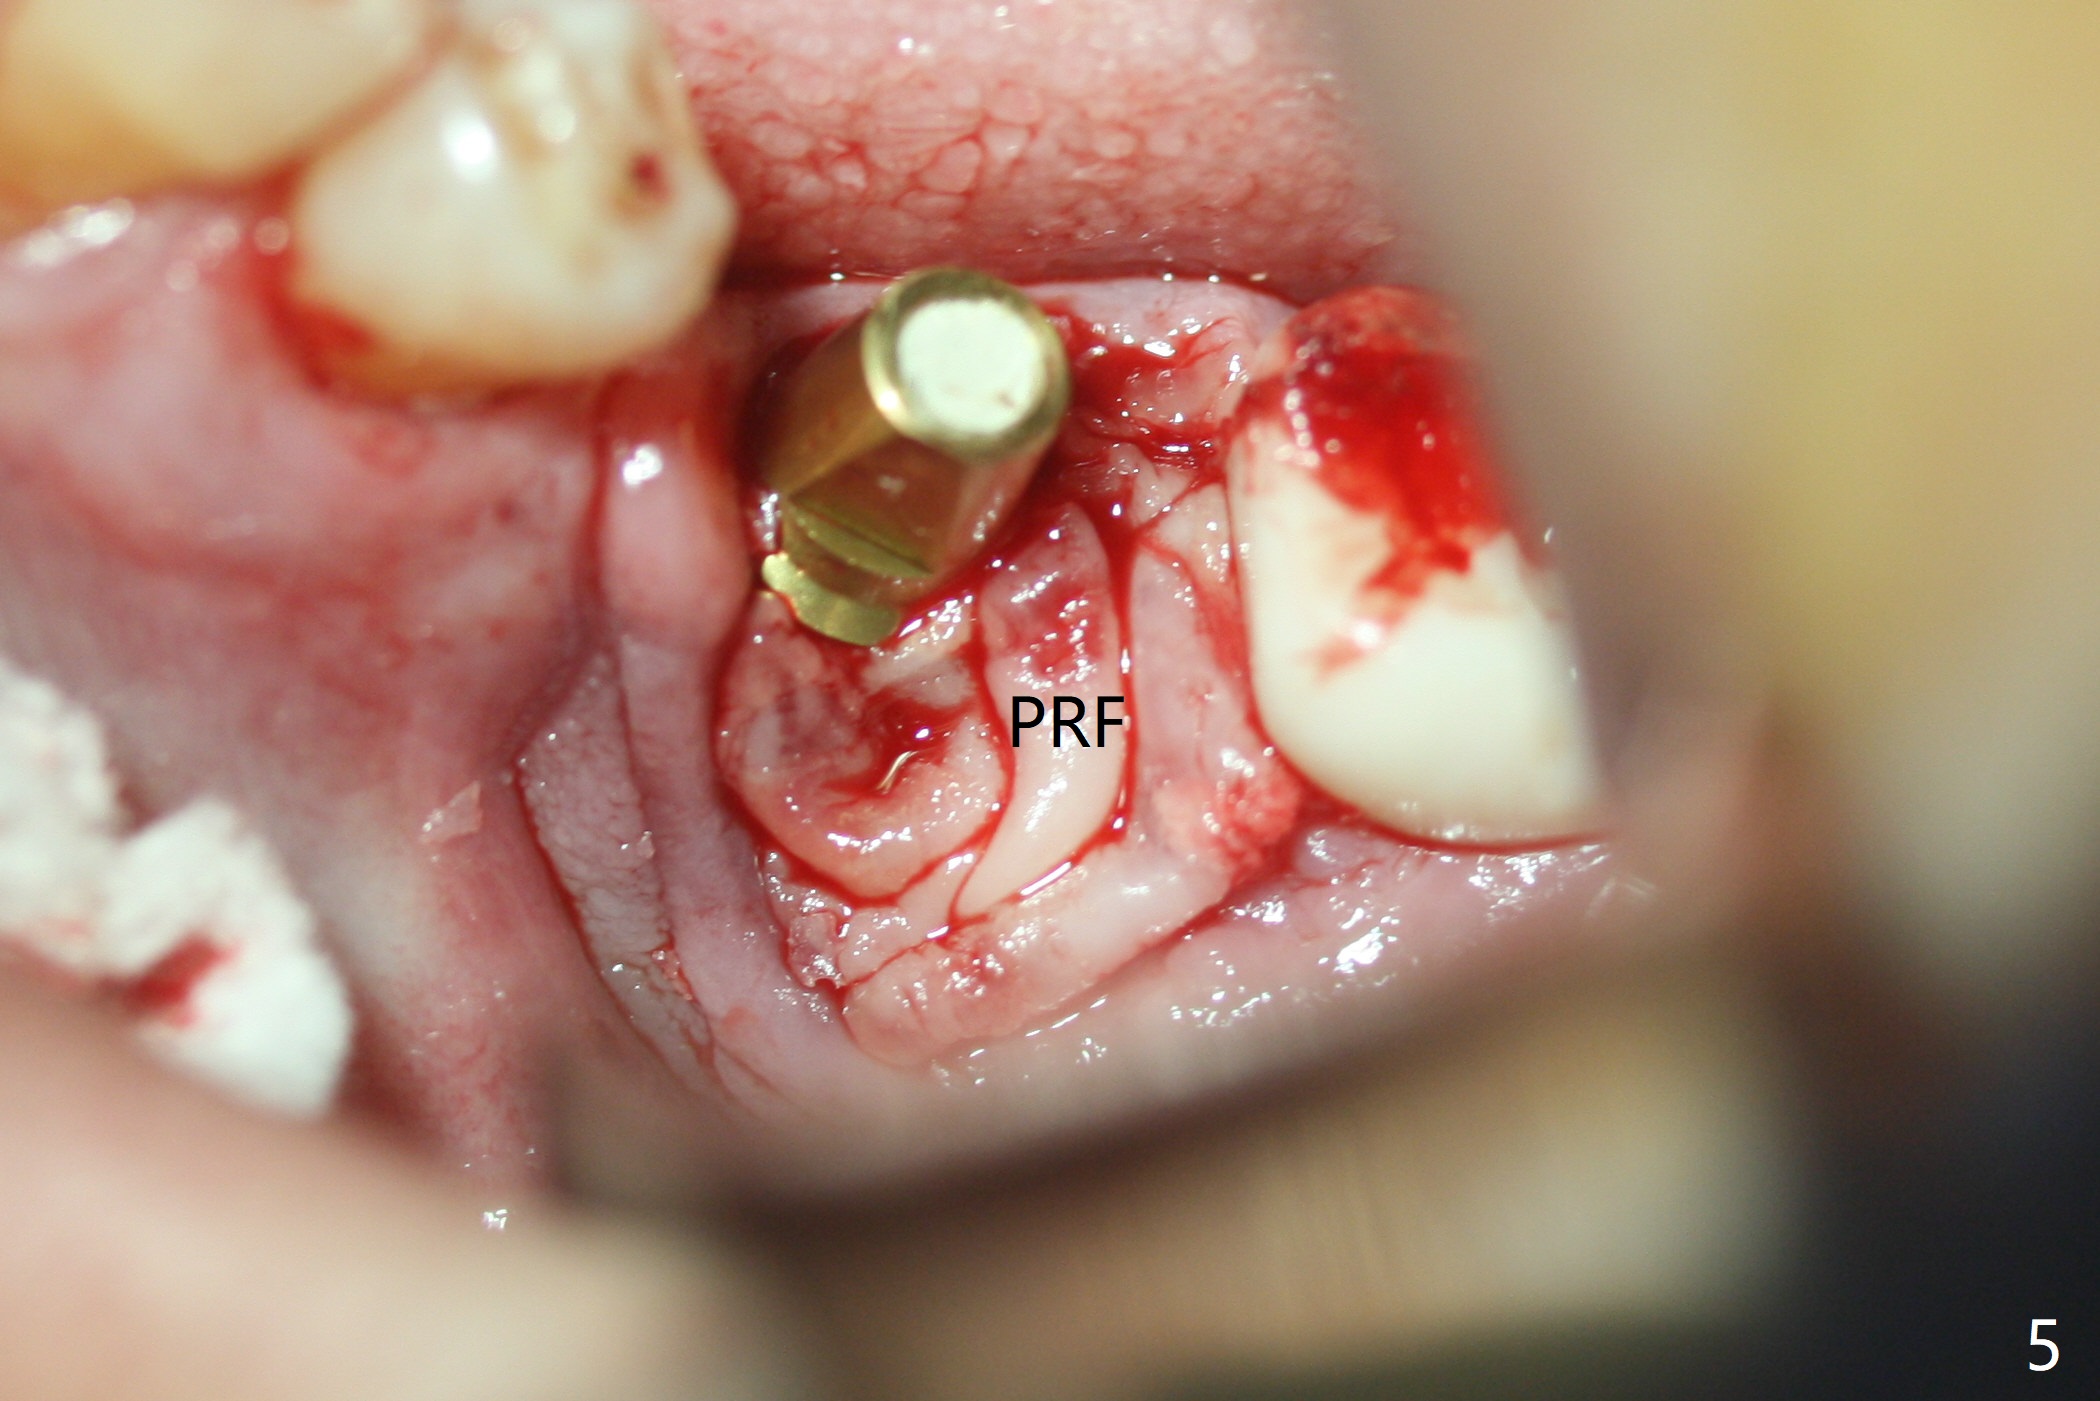

Probably due to severe infection at #19, pain control is difficult. Osteotomy has to be stopped 1.5 mm short of the design. PA taken with a 4.5x10 mm dummy implant does not show the Inferior Alveolar Canal (Fig.1), whereas CT does (Fig.2). With 6 mm clearance, block anesthesia is administered. A 5x10 mm definitive implant is placed with ease (Fig.3). The buccal bony defect is repaired by allograft (Fig.3,4 *), while the soft one by 3 pieces of PRF membrane (Fig.5). The latter is fixed in place by applying setting acrylic as an immediate provisional (Fig.6 P) over the wound, around the abutment (A) and locking into the undercut of the neighboring tooth/implant crown. The patient feels great postop. The gingiva is healthy around the provisional 8 days postop (Fig.7). The patient remains asymptomatic with the healthier gingiva surrounding the simplified provisional 22 days postop, as compared to 8 days postop (Fig.8). The socket heals when the simplified provisional is removed 1.5 months postop (Fig.9-12). The bone graft (Fig.11 ^) seems to have become a part of the regenerated gingiva. The abutment has been dislodged for 2 week (Fig.14 (3 months postop). The bone graft, albeit decreased, is 2 mm subgingival (red dashed line). There is bone distal to the implant 11 months postop (Fig.15 *). There is no bone loss 2 years postop; the UF abutment is completely seated (Fig.16).